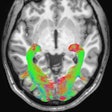

DOPA-PET can alter brain tumor therapy decisions